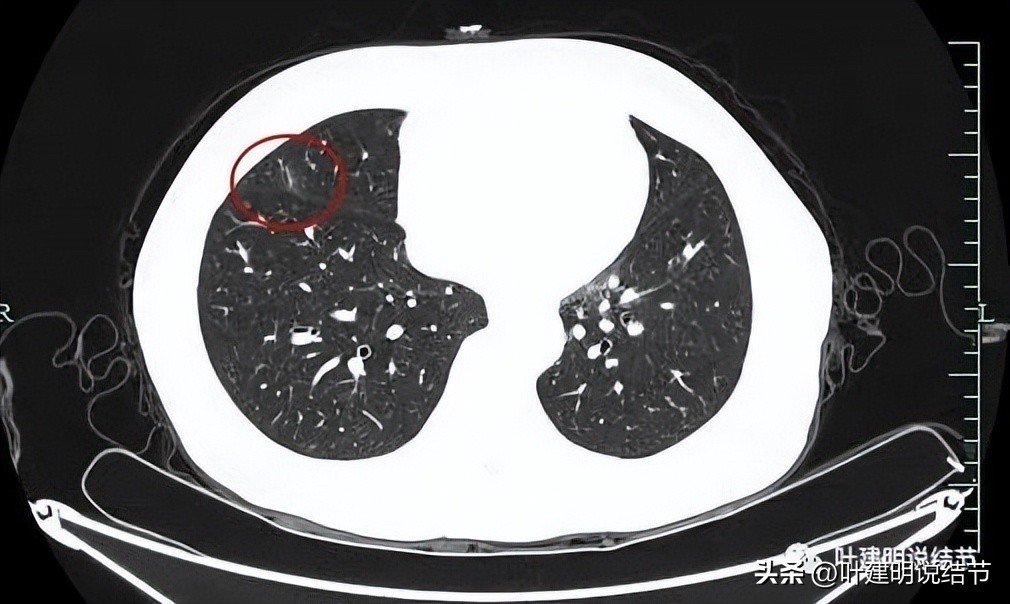

上图显示了病灶轮廓与瘤肺边界其实还是清楚的。

部分边缘有毛刺征可见。

显示明显的血管征与血管异常增粗和壁毛糙。

上图显示病灶轮廓较清,有锐利细毛刺征,灶内有弯曲血管穿行。

囊壁有少许是偏实性成分的,如粉色箭头所示。

血管增粗进入并散开来。

血管在病灶内发出分支。